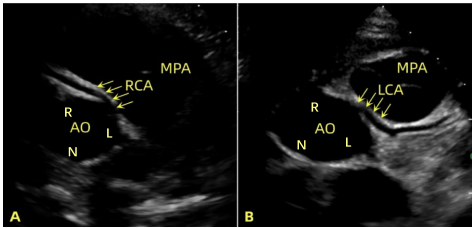

语 本研究针对儿童冠状动脉异常起源伴动脉间走行(AAOCA)缺乏标准化术前影像评估的难题,提出系统性超声诊断框架。通过回顾性分析11例患儿的超声影像,研究人员整合解剖标志(开口偏离、锐角、平行走行征、舒张期血流加速)与功能指标(LVEF、室壁运动),建立可操作性强且无辐射风险的评估方案。结果显示ALCA组LVEF(中位数39.2%)显著低于ARCA组(64.1%,P<0.001),且室壁运动异常更广泛(100% vs. 25%)。该方案能早期识别高危病例(如ALCA合并严重心功能下降),为手术干预提供关键依据,减少儿童对CT等辐射暴露的依赖。

该研究回顾性分析了2017-2022年经手术确诊的11例AAOCA伴动脉间走行患儿(8例ARCA,3例ALCA),平均年龄7.4±3.5岁。研究团队通过超声设备(Philips iE33/CX50)创新性整合四类解剖标志与功能指标:

■ 解剖标志的普适性

所有病例均呈现四大关键征象:

?? 无创优化:四大解剖标志的联合应用(灵敏度91%-100%)显著降低CT使用需求,尤其适合儿童随访

(注:文中所有影像学发现均与CTA结果100%一致,图4-6详见原文)